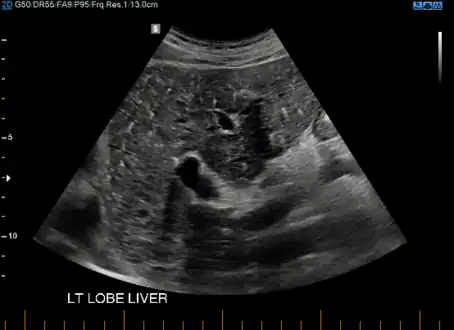

At CT scans, bile duct hamartomas appear as small, well-defined hypo- or isoattenuating masses with little or no enhancement after contrast administration.[2] At MRI, they appear hypointense on T1-weighted images, iso- or slightly hyperintense on T2-weighted images, and hypointense after administration of gadolinium based contrast-agent.[2] On imaging, multiple hamartomas may look similar to metastases or microabscesses.